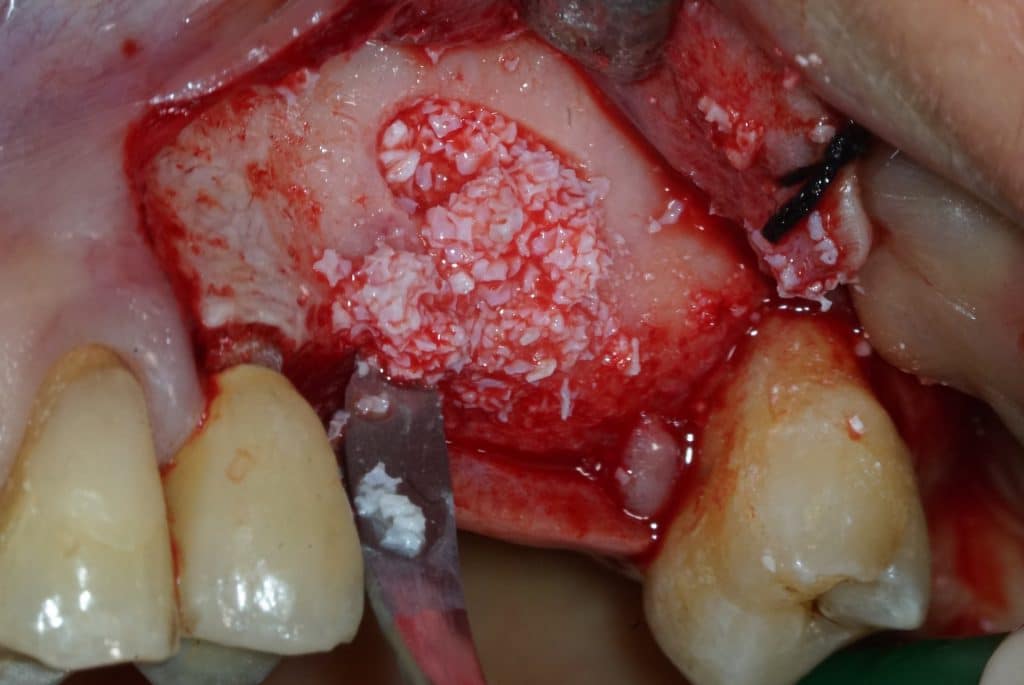

- After the membrane has been detached, a bovine bone substitute (Bio-oss, Geistlich) is inserted.

- Bone filling should be very delicate and gradual

- Before a new application of Bio-Oss it is convenient to create the space with a periosteal elevator

Bio-Oss insertion